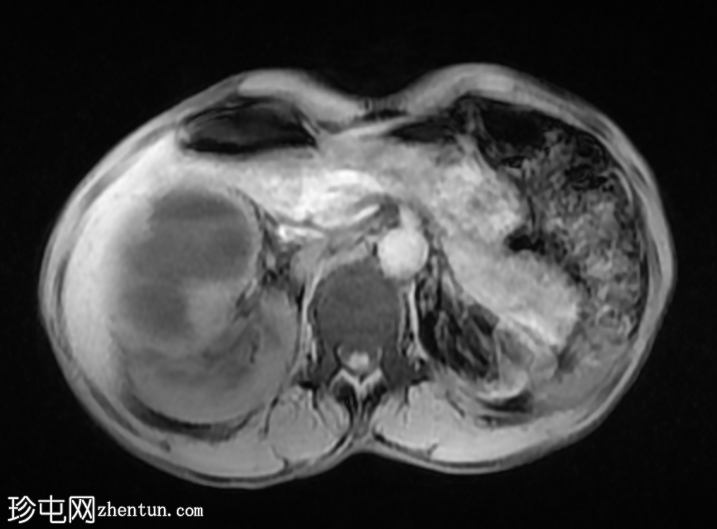

CT

轴位

平扫

右肾前部可见一边界清晰的外生性病变,呈异质性,包含实性及囊性成分,内部可见多发结石。肾周可见模糊影。

左肾体积缩小且萎缩,可见多发结石。

病变内部存在结石及肾周模糊影提示炎症性病变,可能为局灶性黄色肉芽肿性肾盂肾炎(XGP),而非肿瘤性肿块(肾细胞癌)。